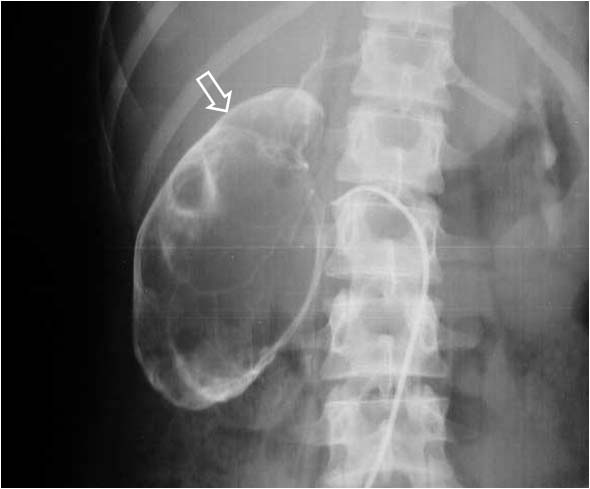

Signo de obstrucción renal en la urografía intravenosa, más frecuente en la uropatía obstructiva crónica. Consiste en el delgado anillo de parénquima renal opacificado que rodea el sistema pielocalicial dilatado, dando un aspecto de pielograma negativo.

Aunque en el caso presentado, el estudio no es una urografía sino una arteriografía, el signo es similar. Vemos una delgada capa de parénquima (flecha) que rodea a los cálices dilatados, en esta fase aún no opacificados.

No debe confundirse este signo con el Signo del borde, aunque tienen semejanzas. En los dos se produce un adelgazamiento de la cortical renal: en el signo del borde está causado por hidronefrosis; en el signo del borde fino se origina por la presencia de una o más masas renales. Tampoco hay que confundirlo con el Signo de los anillos de Dunbar, aunque ambos se ven en la hidronefrosis. El anillo hidronefrótico es el realce cortical mientras que los anillos de Dunbar corresponden al contraste en los túbulos renales.